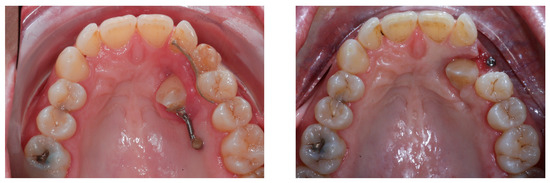

Torque finishing with aligners is the last stage of the treatment, which requires another refinement stage to obtain proper torque and inclination (Figure 6); in this case, a further stage of 18 aligners was necessary. The final occlusion is shown on Figure 7. The final X-ray analysis is presented on Figure 8.

Progress of treatment after canine recovery and before aligner second phase.

Post-treatment intraoral pictures after 18 months of treatment.

Post-treatment panoramic and lateral X-rays. The supernumerary lower tooth will be extracted following patient need in a second time. Cephalometric superimposition shows the torque correction and deep bite resolution.